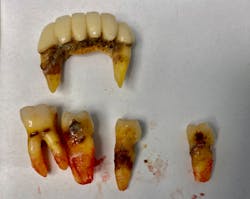

This type of contact can result in caries along the cervical region of the tooth as well as gum and tissue problems.6 Unrestorable caries and/or gum disease can often lead to tooth extraction (figure 2) and, once the addiction is controlled, the need for dentures or dental implants.